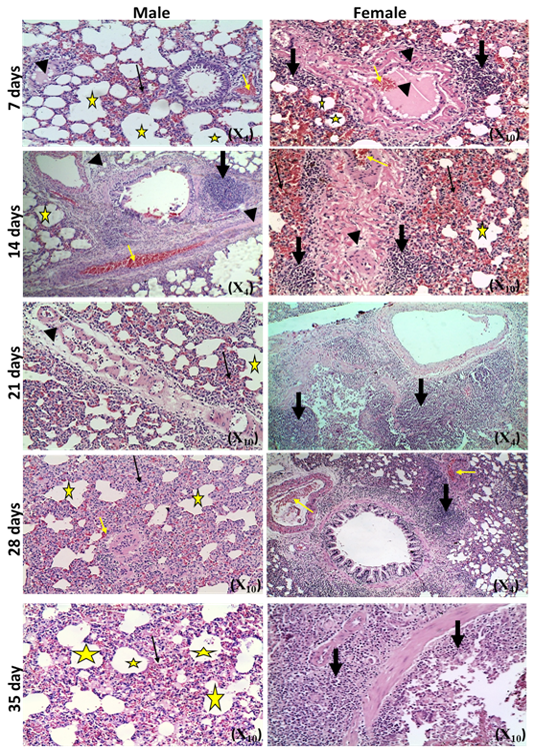

Photomicrographs of lung sections of male and female rats at 7th, 14th, 21st, 28th,and35thday (Haematoxylin and Eosin stain) {congestion (yellow arrow); edema (head arrow), alveolar emphysema (star); inflammatory cells infiltration (thick black arrow); thickening of interstitial tissue (thin black arrow)}.